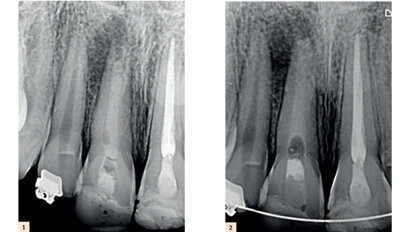

Entre BOPT et BTA : Une étude de cas sur le remodelage du contour gingival de restaurations dento-portées au moyen de couronnes provisoires en résine.

Le remodelage du contour des tissus mous péri-implantaires au moyen de couronnes provisoires en résine après la pose d’un implant...